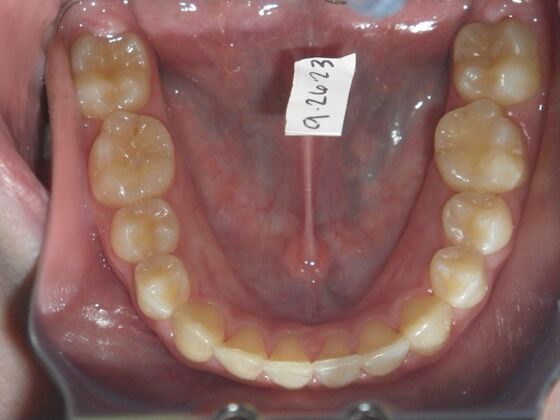

Orthodontics: Case 43

Patient presented with mixed dentition and mild deep overbite, excessive overjet,and rotated lower incisors. She also had a lower bilateral lingual retainer, preventing lower molars from coming forward. She was treated with utility archwires initially, waiting for eruption of cuspids and bicuspids. This was followed by conventional straight wire appliances and upper and lower standard hawley retainers.